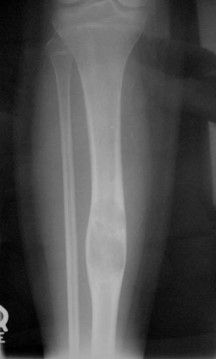

Radiographic Presentation

- Sharply defined osteolytic defect (lobulated, multicystic, or “soap bubble”)

- May be considerable perilesional sclerosis

Sites:

- Predilection for tibia (90%)

- favoring diaphyseal portion of bone